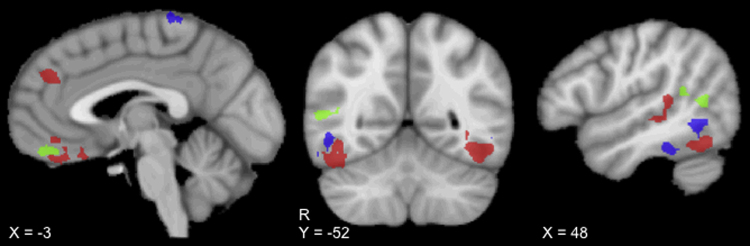

Neuroimaging studies of the perception of point-light displays of biological motion had focused on adolescent and adult participants until our group recently extended this work to children as young as 4 years of age (Table 2). In this fMRI study, we identified common and distinct brain mechanisms for biological motion perception in children with ASD and their unaffected siblings (US) relative to typically developing (TD) children without a first- or second-degree relative with ASD (Kaiser et al., 2010b). The unique three group design allowed us to identify three types of neural signatures of autism: (1) “state regions,” dysfunction in brain mechanisms unique to the children with ASD; (2) “trait regions,” disrupted neural circuitry shared by the US and children with ASD; and, (3) “compensatory activity,” the recruitment of additional brain areas during a social perception task by the US. As illustrated in Fig. 2, conjunction analyses of the differential activation to biological motion relative to scrambled motion identified state activity (red color map) localized to the left ventrolateral prefrontal cortex, right amygdala, right posterior superior temporal sulcus, ventromedial prefrontal cortex, and bilateral fusiform gyri. Trait activity (blue color map) was localized to bilateral fusiform gyrus, left dorsolateral prefrontal cortex, and right inferior temporal gyrus. Compensatory activity (green color map) was localized to the right posterior superior temporal sulcus and the ventromedial prefrontal cortex.

Fig. 2.

Neural signatures of autism revealed by conjunction analyses of the biological motion > scrambled motion contrasts. State activity (TD > ASD ∩ US > ASD; red map) was localized to the left ventrolateral prefrontal cortex, right amygdala, right posterior superior temporal sulcus, ventromedial prefrontal cortex, and bilateral fusiform gyri. Trait activity (TD > ASD ∩ TD > US; blue map) was localized to the bilateral fusiform gyri, left dorsolateral prefrontal cortex, and right inferior temporal gyrus. Compensatory activity (US > TD ∩ US > ASD; green map) was localized to the right posterior superior temporal sulcus and ventromedial prefrontal cortex. (For interpretation of the references to color in this figure legend, the reader is referred to the web version of the article.)

Although disorder heterogeneity is an important challenge for ASD research, the neural response to biologically-relevant social stimuli clearly differentiated children with and without the disorder, reflecting the robust nature of the typical response to such stimuli and the centrality of social deficits and associated brain dysfunction in ASD (Pelphrey et al., 2011). The state regions characterize the nature of disruption in social brain circuitry in young children with ASD, extending work with older populations (Freitag et al., 2008, Herrington et al., 2007). Future studies should aim to establish key factors resulting in atypical activity in the state regions in individuals with ASD. For example, aberrant gaze behavior may contribute to differential response to the biological motion stimuli in children with ASD; although initial eye-tracking analyses indicate equivalent time spent viewing both coherent and scrambled biological motion stimuli by children with and without ASD in a new group of subjects (Kaiser et al., 2011). It is interesting to note that whereas studies of adults primarily localized hypoactivation in ASD groups to posterior superior temporal regions, our state regions included several nodes of the social brain: the right posterior superior temporal sulcus and bilateral fusiform gyri as well as frontal areas and limbic structures including ventromedial prefrontal cortex, left ventrolateral prefrontal cortex, and the right amygdala. This work increases our ability to chart the atypical development of disrupted brain mechanisms for biological motion perception into early childhood. Yet, the participants in our study were only as young as 4 years of age. Since ASD emerges in the first year of life, the hypoactivation in the state regions could reflect the result of living with ASD. The trait activity cannot be explained in this way.

Trait regions likely reflect the genetic vulnerability to develop ASD, as these are areas of dysfunction in US and children with ASD. Thus, these regions represent a potential neuroendophenotype, and therefore provide a novel means of overcoming genomic complexity and disorder heterogeneity in identifying genetic liability for the disorder. In line with Gottesman and Gould's definition of endophenotypes (2003), trait activations in the left dorsolateral prefrontal cortex, right inferior temporal gyrus, and bilateral fusiform gyri, emerged during a social perception task relating to a core deficit in ASD and were shared between affected individuals (ASD) and first-degree relatives (US). It is important to note that we explicitly ruled out the broad autism phenotype in the US. This limits the possibility that the brain function in this group reflects the developmental outcome of living with autistic-traits. This finding presents a rich opportunity for future studies to apply this quantitative endophenotype to inform genome-wide association studies to identify candidate genetic mechanisms and associated pathophysiological pathways.

The finding of compensatory activity, areas of enhanced activity unique to the US, suggests that the genetic risk for ASD can result in both disruptions in brain mechanisms for processing biological motion (trait activity) and related recovery from this risk in the form of additional neural involvement for normative social function. Notably, the compensatory activity was localized to the ventromedial prefrontal cortex and the right posterior superior temporal sulcus, regions that support social perception and social cognition (e.g. Adolphs, 1999, Allison et al., 2000, Puce and Perrett, 2003). Future studies are needed to characterize the origins of the compensatory activity. We posit that the engagement of additional brain mechanisms represents the result of a developmental process, likely influenced by genetic and environmental factors. Since the magnitude of activation in these regions did not correlate with age in the original sample and, thus, is present by 4 years of age, this process likely occurs very early in development. It is possible that compensatory activity reflects protective genetic factors in addition to the genetic liability in US exhibited by trait activity. It will be important for future studies to characterize the genetic contributions to variability in activation levels within these regions. In addition, research is needed to compare activity in these regions in US participants with and without the broad autism phenotype (BAP; Hurley et al., 2007), to determine the function and etiology of this brain response to biological motion. The most striking implication of the finding of compensatory activity is that these regions could serve as targets for intervention and, with further study, lead to a better understanding of the mechanisms through which successful treatments function.